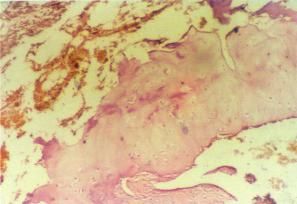

超微結構研究表明,棉酚引起線粒體腫脹,嵴斷裂、固縮、嚴重空泡化及潰破等。線粒體是細胞呼吸、能量供應和氧化、磷酸化的重要細胞器,線粒體損傷導致細胞死亡[10,11]。